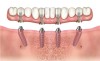

Fig 9. Dual-axial maxillary implant solutions to mitigate need for sinus augmentation and onlay grafts.

Figure 9

Fig 11. Panorex of clinical application of dual-axis principles. From left to right: 36-degree tooth No. 4; 24-degree tooth No. 6; 12-degree tooth No. 8; 12-degree tooth No. 9; 24-degree tooth No. 11; and 36-degree tooth No. 13. Angulation is designed to avoid maxillary sinus and buccal constraints of the anterior maxilla. (Image courtesy of Costa Nicolopoulos, BDS, Dubai, United Arab Emirates)

Figure 11

With the increased application of this concept, more options have been introduced, including 24-degree and 36-degree correction (Figure 11 through Figure 13). At present, larger angular corrections are available with external hexagon connection systems, while the 12-degree connection is also available in most internal connection configurations.